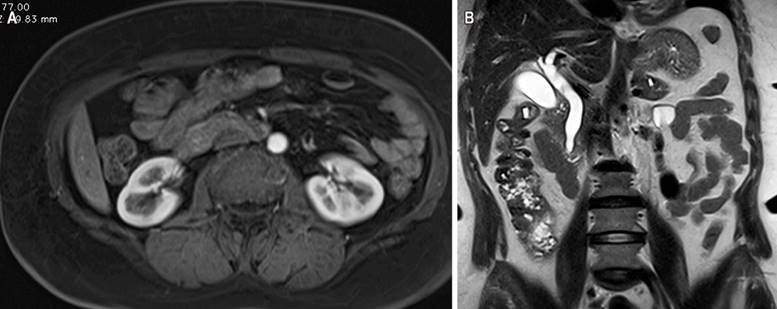

This is a 58-year-old woman with a history of hypertension and diabetes mellitus who does not require insulin and who consulted after 20 days of abdominal pain in the left hypochondrium, stabbing type, that expanded to the epigastrium with an intensity 6/10 on the analogous scale of pain associated with generalized jaundiced dye, acolia, choluria, and febrile peaks quantified up to 39 ºC. She underwent some laboratory studies that evidenced hyperbilirubinemia at the expense of direct bilirubin and elevated transaminases. The ultrasound showed hepatic steatosis, the gallbladder without stones inside associated with dilated intra- and extrahepatic bile duct with a common bile duct of 12 mm but did not show the cause of the obstruction. She also underwent a computed tomography (CT) scan and magnetic resonance cholangiopancreatography (Figure 1), which showed dilation of the bile duct secondary to distal choledocholithiasis, and it was decided to take her to endoscopic retrograde cholangiopancreatography (ERCP) to perform the management of obstructive biliary syndrome that had a probable biliary origin. However, a large papilla of neoplastic appearance of 3 centimeters at its greatest diameter was found without canalizing the bile duct. The patient underwent a biopsy and magnetic resonance imaging with double contrast (Figure 2) that reported choledocholithiasis, dilatation of the intra- and extrahepatic bile duct, and dilation of the intrapancreatic duct due to probable periampullary neoplasia.

Figure 2 Magnetic resonance imaging contrasted with evidence of dilatation in the intra- and extrahepatic bile duct secondary to periampullary lesion (A) in the axial section and (B) coronal section. Source: Authors’ archive.